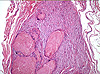

CASO N° 1 (Dr. Jair e Dr. Delgado)

Paciente do gênero masculino, 44 anos de idade, apresenta uma lesão no palato duro e palato mole.